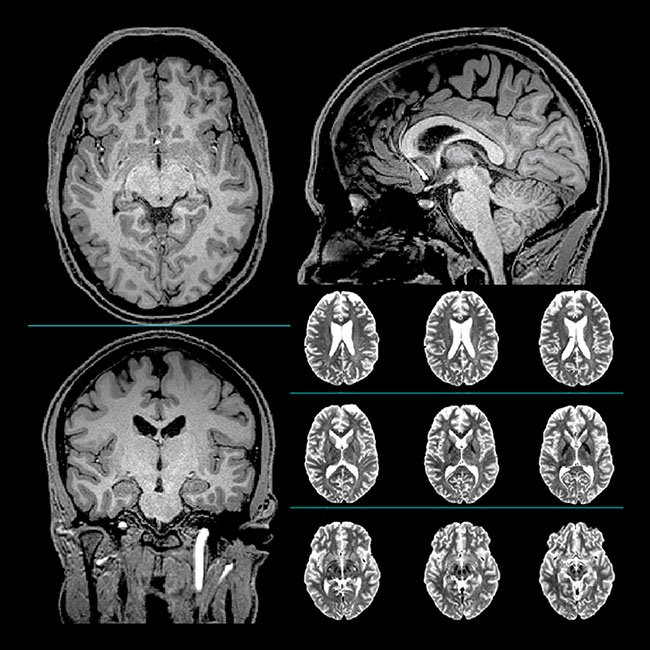

MRI brain baseline Chao study 2020The loss of brain cells from brain injuries is a well-documented phenomenon. In moderate to severe cases of brain injuries, the generalized loss could amount to 5% of brain cells per year. These are cells that include those in the areas of the brain that affect cognition and memory functions. In a recent study, a professional hockey player, with multiple concussions and generalized loss or atrophy of the brain cells, was observed. These deficiencies were the results of injuries received during his hockey career. Professor Linda Chao of the University of California San Francisco (UCSF) was the lead investigator in the study. The subject was treated with two Vielight transcranial-intranasal devices — the Neuro Gamma, followed by the Neuro Alpha, over a period of eight weeks.

The results of this study showed improvements in learning, memory, executive functions, attention, and mental processing speed. This is a very significant finding because, for the first time ever, a study was able to show measurable growth of gray matter due to transcranial photobiomodulation (tPBM), in some important areas of the brain, in a human. The growth was present in the hippocampus and thalamic areas.

Indeed, the study provides significant evidence that PBM helps the brain to repair itself!  Magnetic resonance imaging (MRI) was used to measure the growth of neurons. In addition to growth and repair of damage in the brain cells, the brain was observed to perform more efficiently.